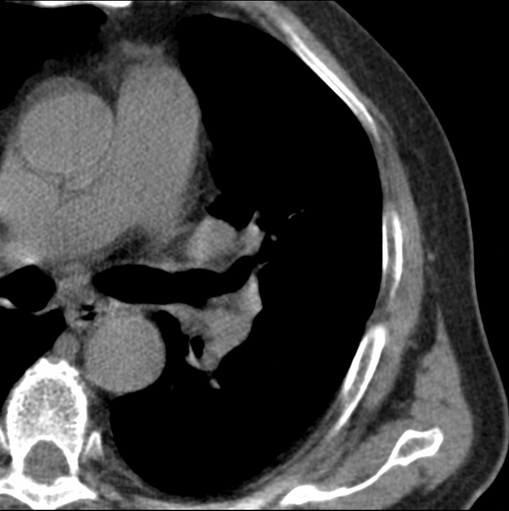

标题: CT25434:胸部CT增强扫描

男性患者 81岁 咳嗽 咳痰 咯血

左肺中心型肺癌并:1.左肺阻塞性肺炎;2.纵隔淋巴结肿大;

肿块贴近左肺门,包绕左上肺动脉,形态不规则。肿块增强扫描中度强化。纵膈内主动脉弓左旁间隙、气管隆突前、下间隙见多枚淋巴结影。综上考虑左侧中央型肺癌可能性大。图片没有完整上传,尤其是左肺上叶支气管分支层面没有上传,因此不好判断是叶支气管中断还是段支气管中断。另外,下图红色部分所示是“黏液支气管征”吗?